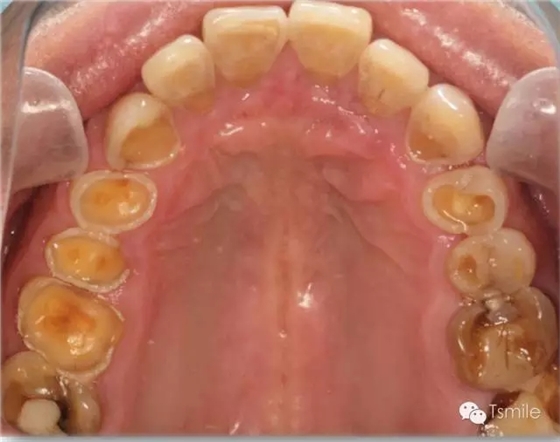

圖4: 神經(jīng)性貪食癥導(dǎo)致的上頜前牙舌側(cè)重度磨耗

神經(jīng)性貪食癥是患者由于心理性原因在飲食后自我催吐,混有胃液的嘔吐物進(jìn)入口腔內(nèi),接觸牙齒表面,對(duì)牙齒硬組織造成嚴(yán)重酸蝕脫礦。由于患者在嘔吐時(shí)的特定體位,神經(jīng)性貪食癥導(dǎo)致的牙列重度磨耗主要發(fā)生于上前牙的舌側(cè)、或者累積上頜前磨牙的舌面。